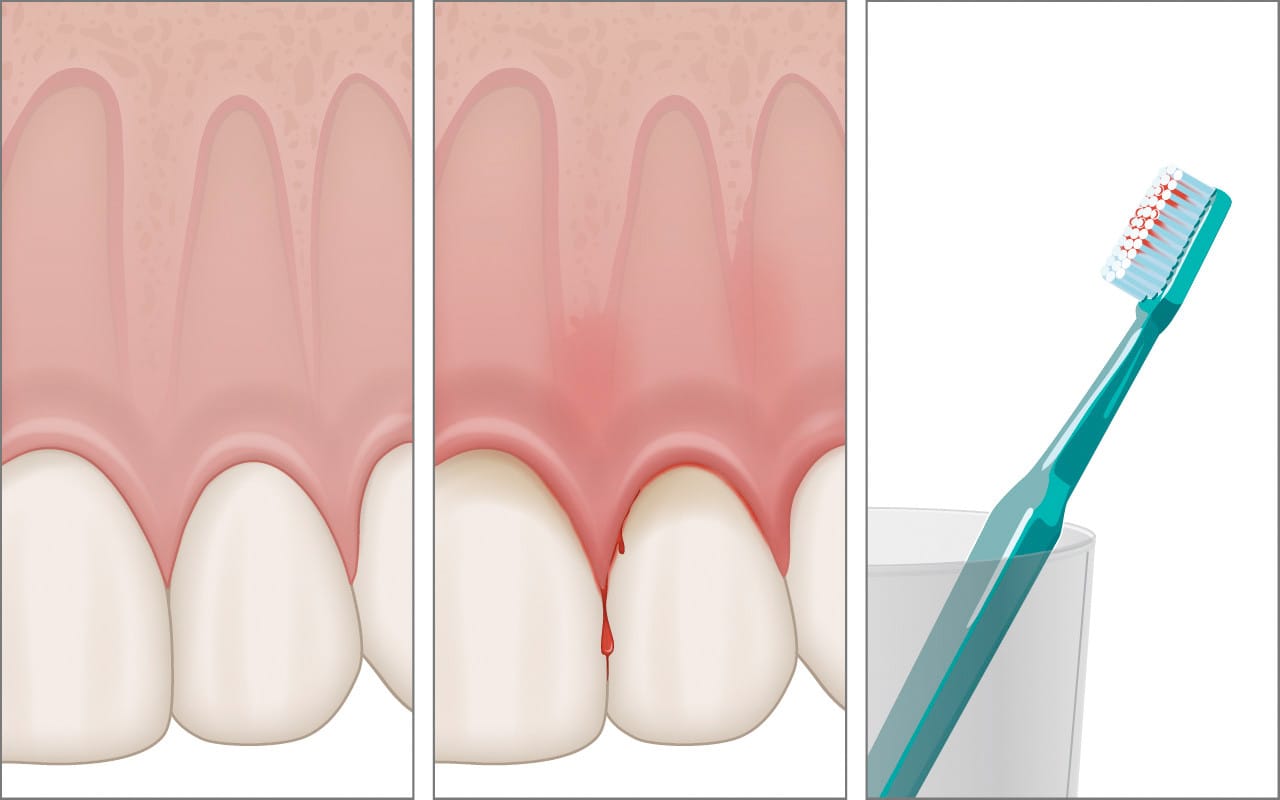

Saignement des gencives

Le saignement est souvent le premier signe d’inflammation.

Contrairement à une idée reçue, il ne faut pas arrêter le brossage : il faut au contraire optimiser la technique et le nettoyage interdentaire. Si le saignement persiste, un examen au cabinet est recommandé.